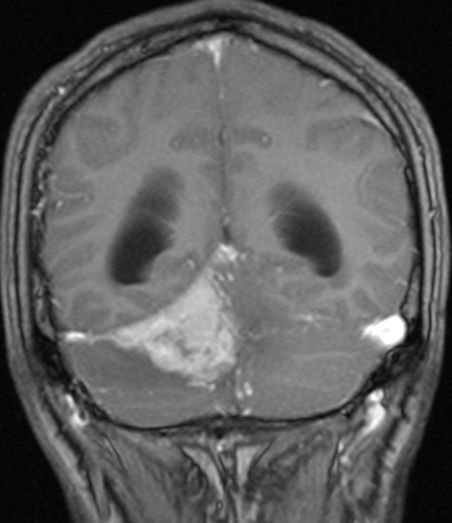

Klinik Scharf begrenzt, homogen, extraaxiale Raumforderung. Breite Verbindung zur Dura. Nach KM homogenes Enhancement. 20% Verkalkungen oder Schädelveränderungen (Hyperostose, Osteolyse). Wenn alle Kriterien erfüllt sind, ist eine histologische Sicherung entbehrlich.

Diagnostik Fallbeispiele

sekretorisches M. seltene, gutartige Sonderform. In 70% starkes perifokales Hirnödem, in 50% hemisphaerisches Hirnödem. Überwiegend ältere Patienten. Typisch basaler Sitz.